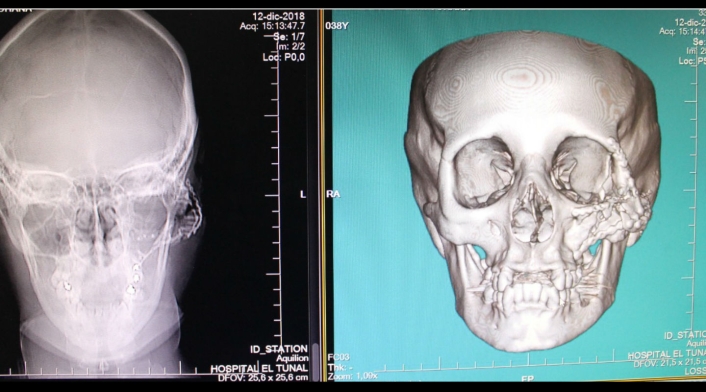

“Nini Johanna sufrió una gran destrucción de las cavidades orbitarias encargadas de alojar los globos oculares, generando que su ojo izquierdo se saliera de su posición natural y dejando su pómulo en pedazos y con una deformación en la estética de su cara, por lo cual, a la paciente, se le realizó un procedimiento complejo”, señaló Lina Rincón, cirujana maxilofacial de la USS El Tunal.

La médico cirujana explicó que en la primera intervención quirúrgica se le practicó la corrección de la simetría de los ojos en la cara y la apertura bucal generada por la herida causada por el proyectil.

Ya en la segunda cirugía se reconstruyó el pómulo, incrustando más de 20 tornillos de titanio en el rostro, placas y material de osteosíntesis, para fijar las fracturas de la cara.